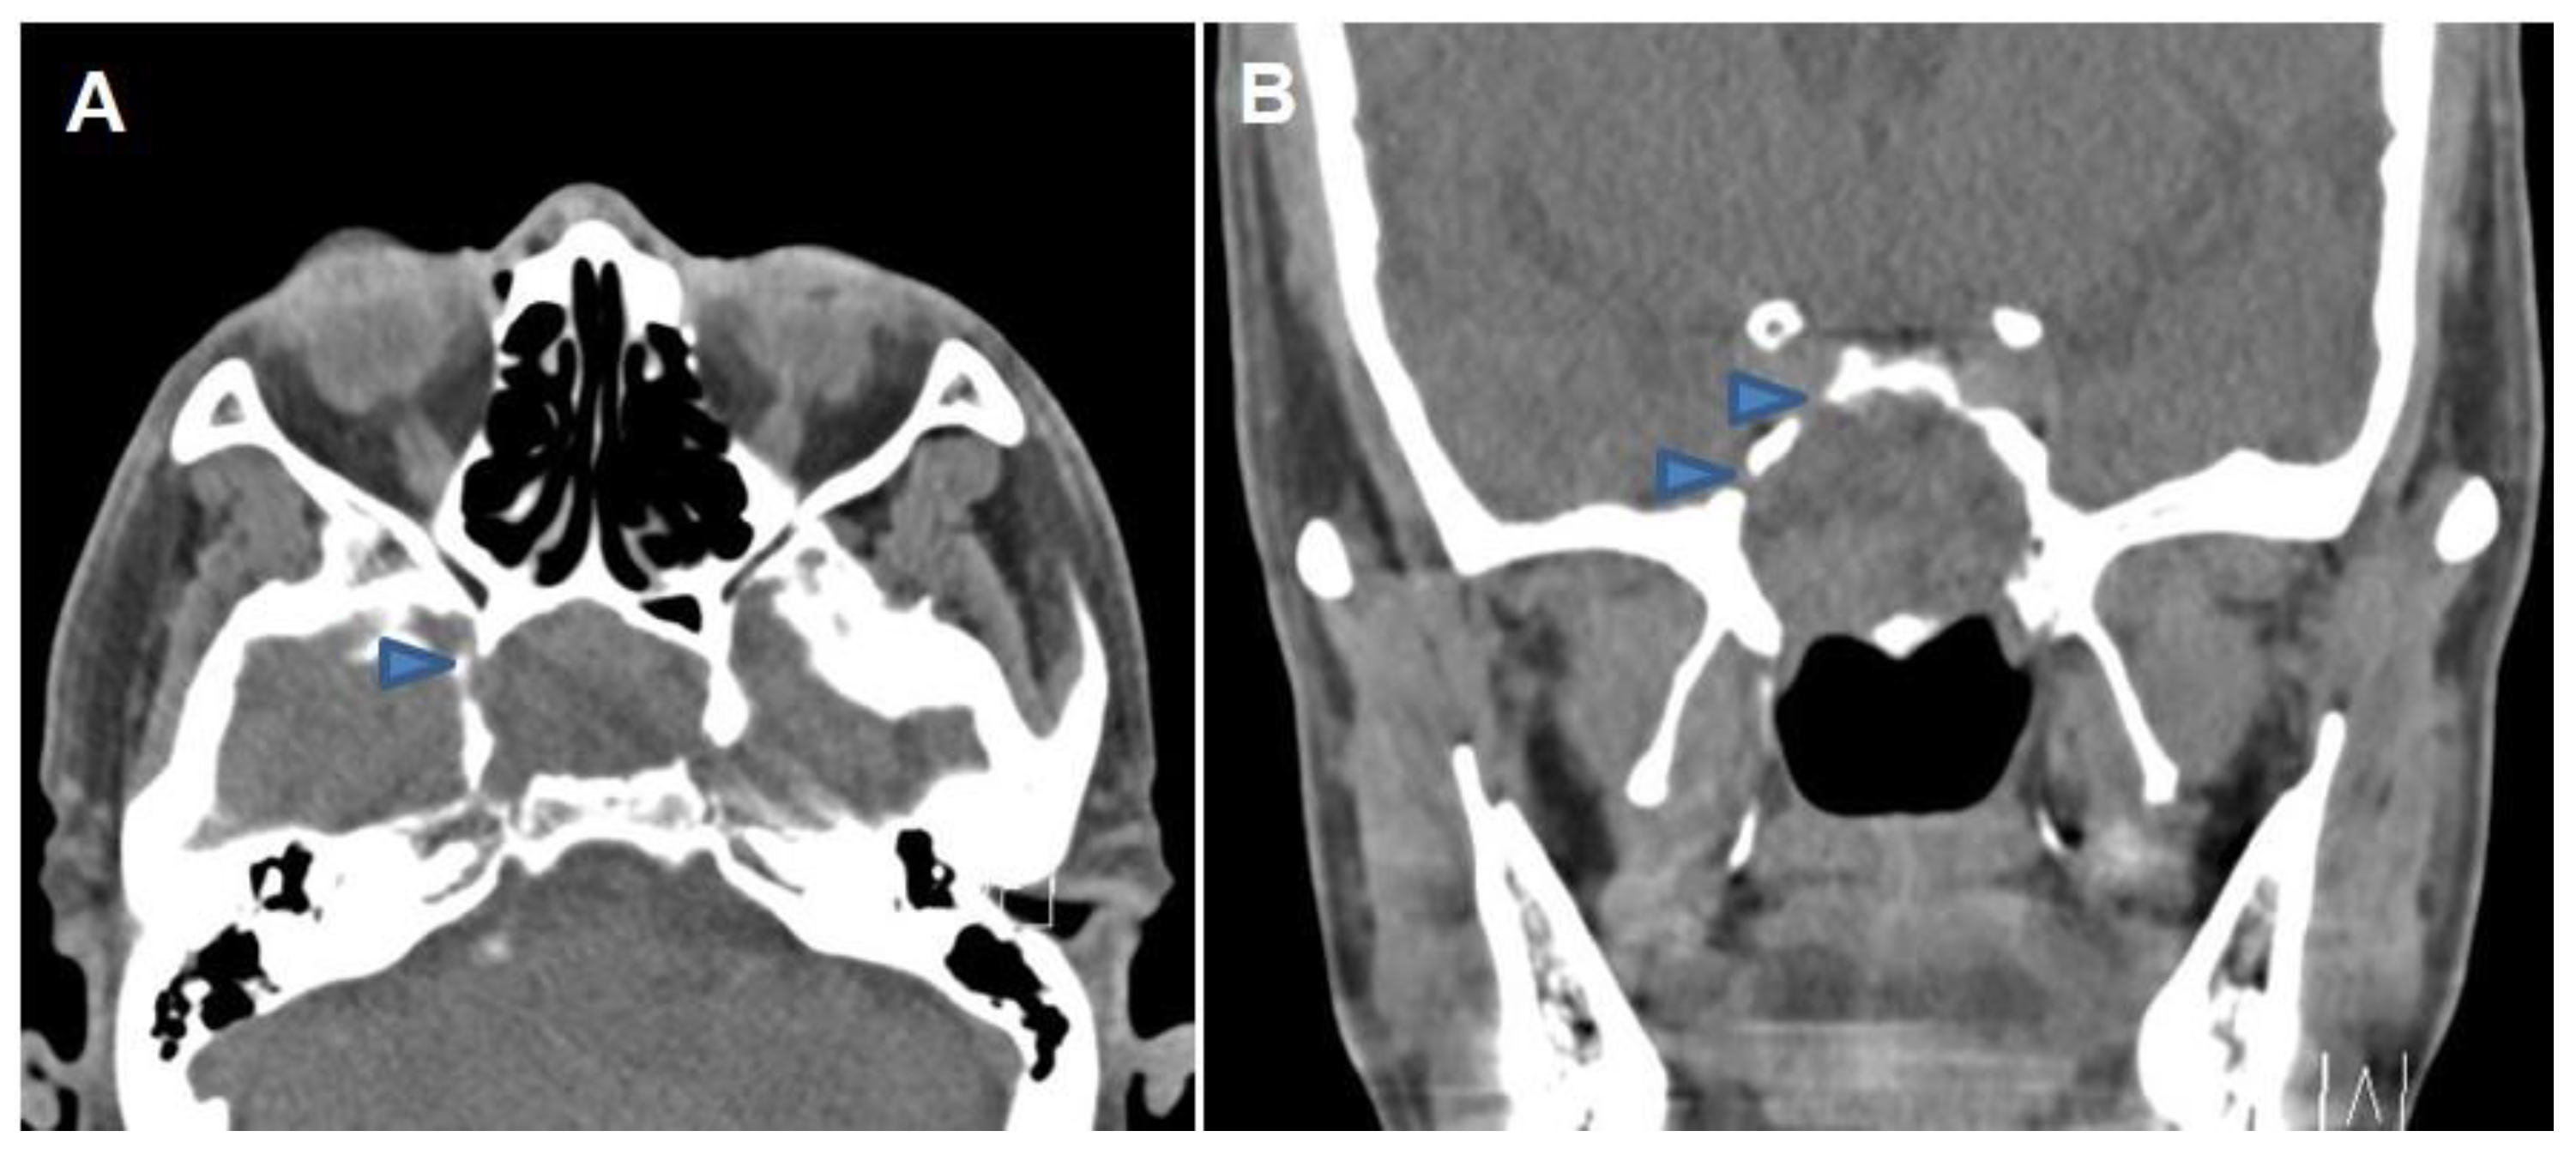

2. Case Report